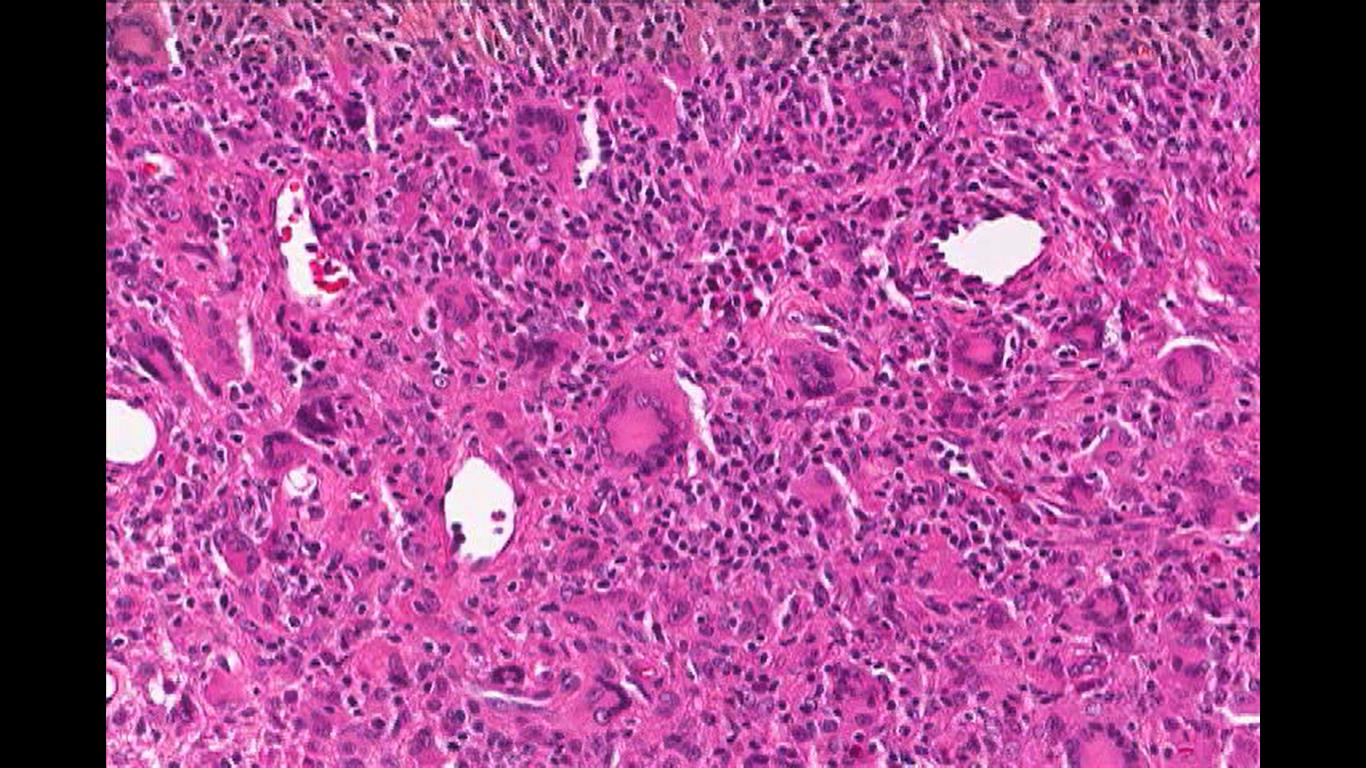

Erdheim-Chester disease is characterized by diffuse infiltration of the long bones, heart, lungs, kidneys, and retroperitoneum by histiocytes and lipid-laden macrophages. Histopathology classically demonstrates fibrosing xanthogranulomas with foamy histiocytes and Touton giant cells (image 1). Immunohistochemistry reveals that these cells express the histiocyte marker CD68, CD163 and Factor XIIIa, but unlike Langerhans cell histiocytosis (LCH), they do not express CD1a or S100, which is a key differentiating factor. Additionally, ECD cells lack of Birbeck granules.

Image 1: Touton Giant Cell, a foamy lipid laden macrophage. Image courtesy of Dr. William Morris, M.D.